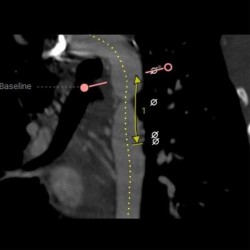

L'anévrisme aortique est une dilatation d'une partie de l'aorte du thorax. C'est la plus grande artère du corps humain, partant du coeur, il traverse le thorax, puis descend jusqu'à l'abdomen, où il se ramifie pour alimenter les membres inférieurs. Si un anévrisme est détecté dans cette zone, le seul traitement est la chirurgie ouverte, réalisée sous anesthésie générale. Suite à l’intervention médicale en chirurgie de l'aorte Tunisie, le patient doit rester à la clinique pendant une période minimale de 4 à 7 jours.

- opération chirurgie de la crosse aortique

La chirurgie ouverte est la méthode de référence pour traiter toute pathologie de la crosse aortique. Chez les personnes agées, des anomalies aortiques sont couramment apparaissent :